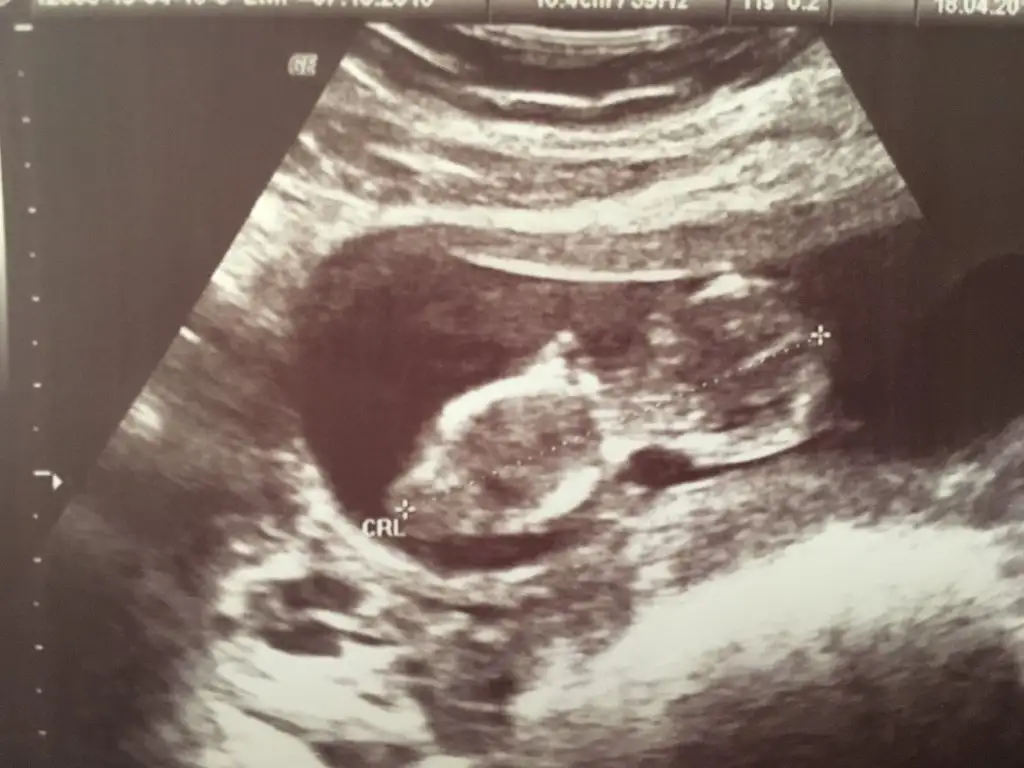

Cinsiyet tahmininde bulunmak isteyen var mı kızlar :))

Eklentiler

• 873283E9-375F-409B-A32B-EF8602747237.webp

873283E9-375F-409B-A32B-EF8602747237.webp

29,5 KB · Görüntüleme: 65